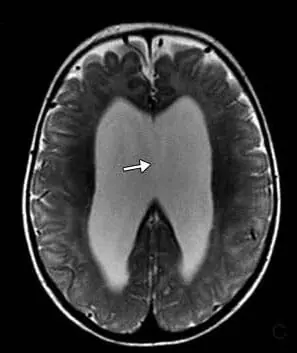

頭部磁気共鳴映像法では、テント上水頭症、視交叉陥凹のバルーニング、薄い脳梁、側脳室および第3脳室の拡張、透明中隔の欠如、および脳の低髄鞘化が明らかになった(図2)。

図2. 磁気共鳴画像法T2強調矢状画像。 脳梁は薄かった。 磁気共鳴画像法T2強調冠状断像。